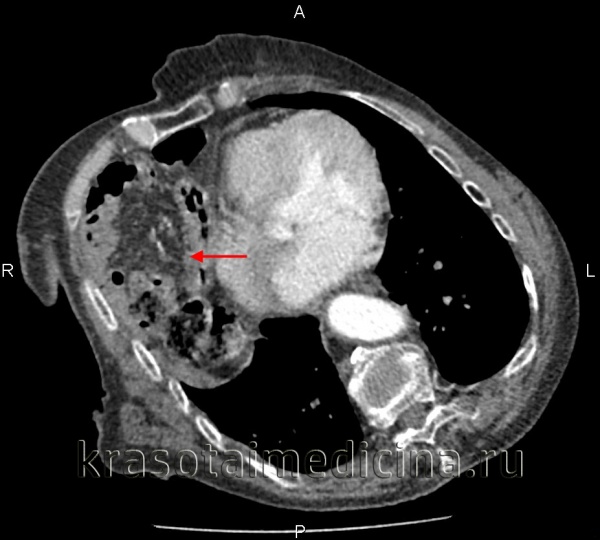

(Слева) На аксиальной КТ с контрастным усилением определяется глубокий разрыв селезенки и активная экстравазация. Обратите внимание на разрыв нижнего полюса селезенки, где обнаруживается участок высокой плотности, свидетельствующий об артериальной экстравазации.

(Справа) На аксиальной КТ с контрастом у этой же пациентки определяется большая гематома около селезенки, а также признаки интенсивной артериальной экстравазации.